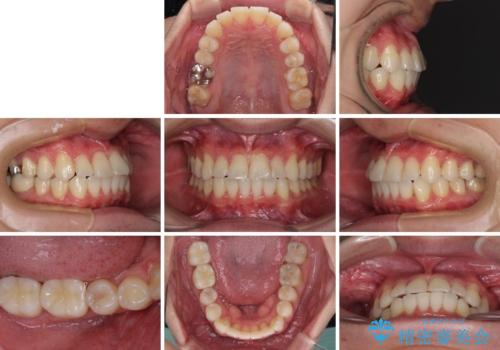

- 30代男性

- 矯正装置

- 審美装置

- 治療期間

- 1年2ヶ月

- 右下奥歯の虫歯がしみて痛いとのことで来院された患者様です。

神経近くにまで及ぶ大きな虫歯でしたが、速やかに処置を行い、痛みは即日解消されました。

虫歯が大きかったため、クラウンによる補綴治療が必要になる旨をお伝えしたところ、矯正治療にも興味があるとのことでした。

短期間で手間のかからない方法がご希望でしたので、ワイヤー装置による矯正治療を行うこととし、矯正治療後に右奥2歯をセラミッククラウンにて補綴することとしました。